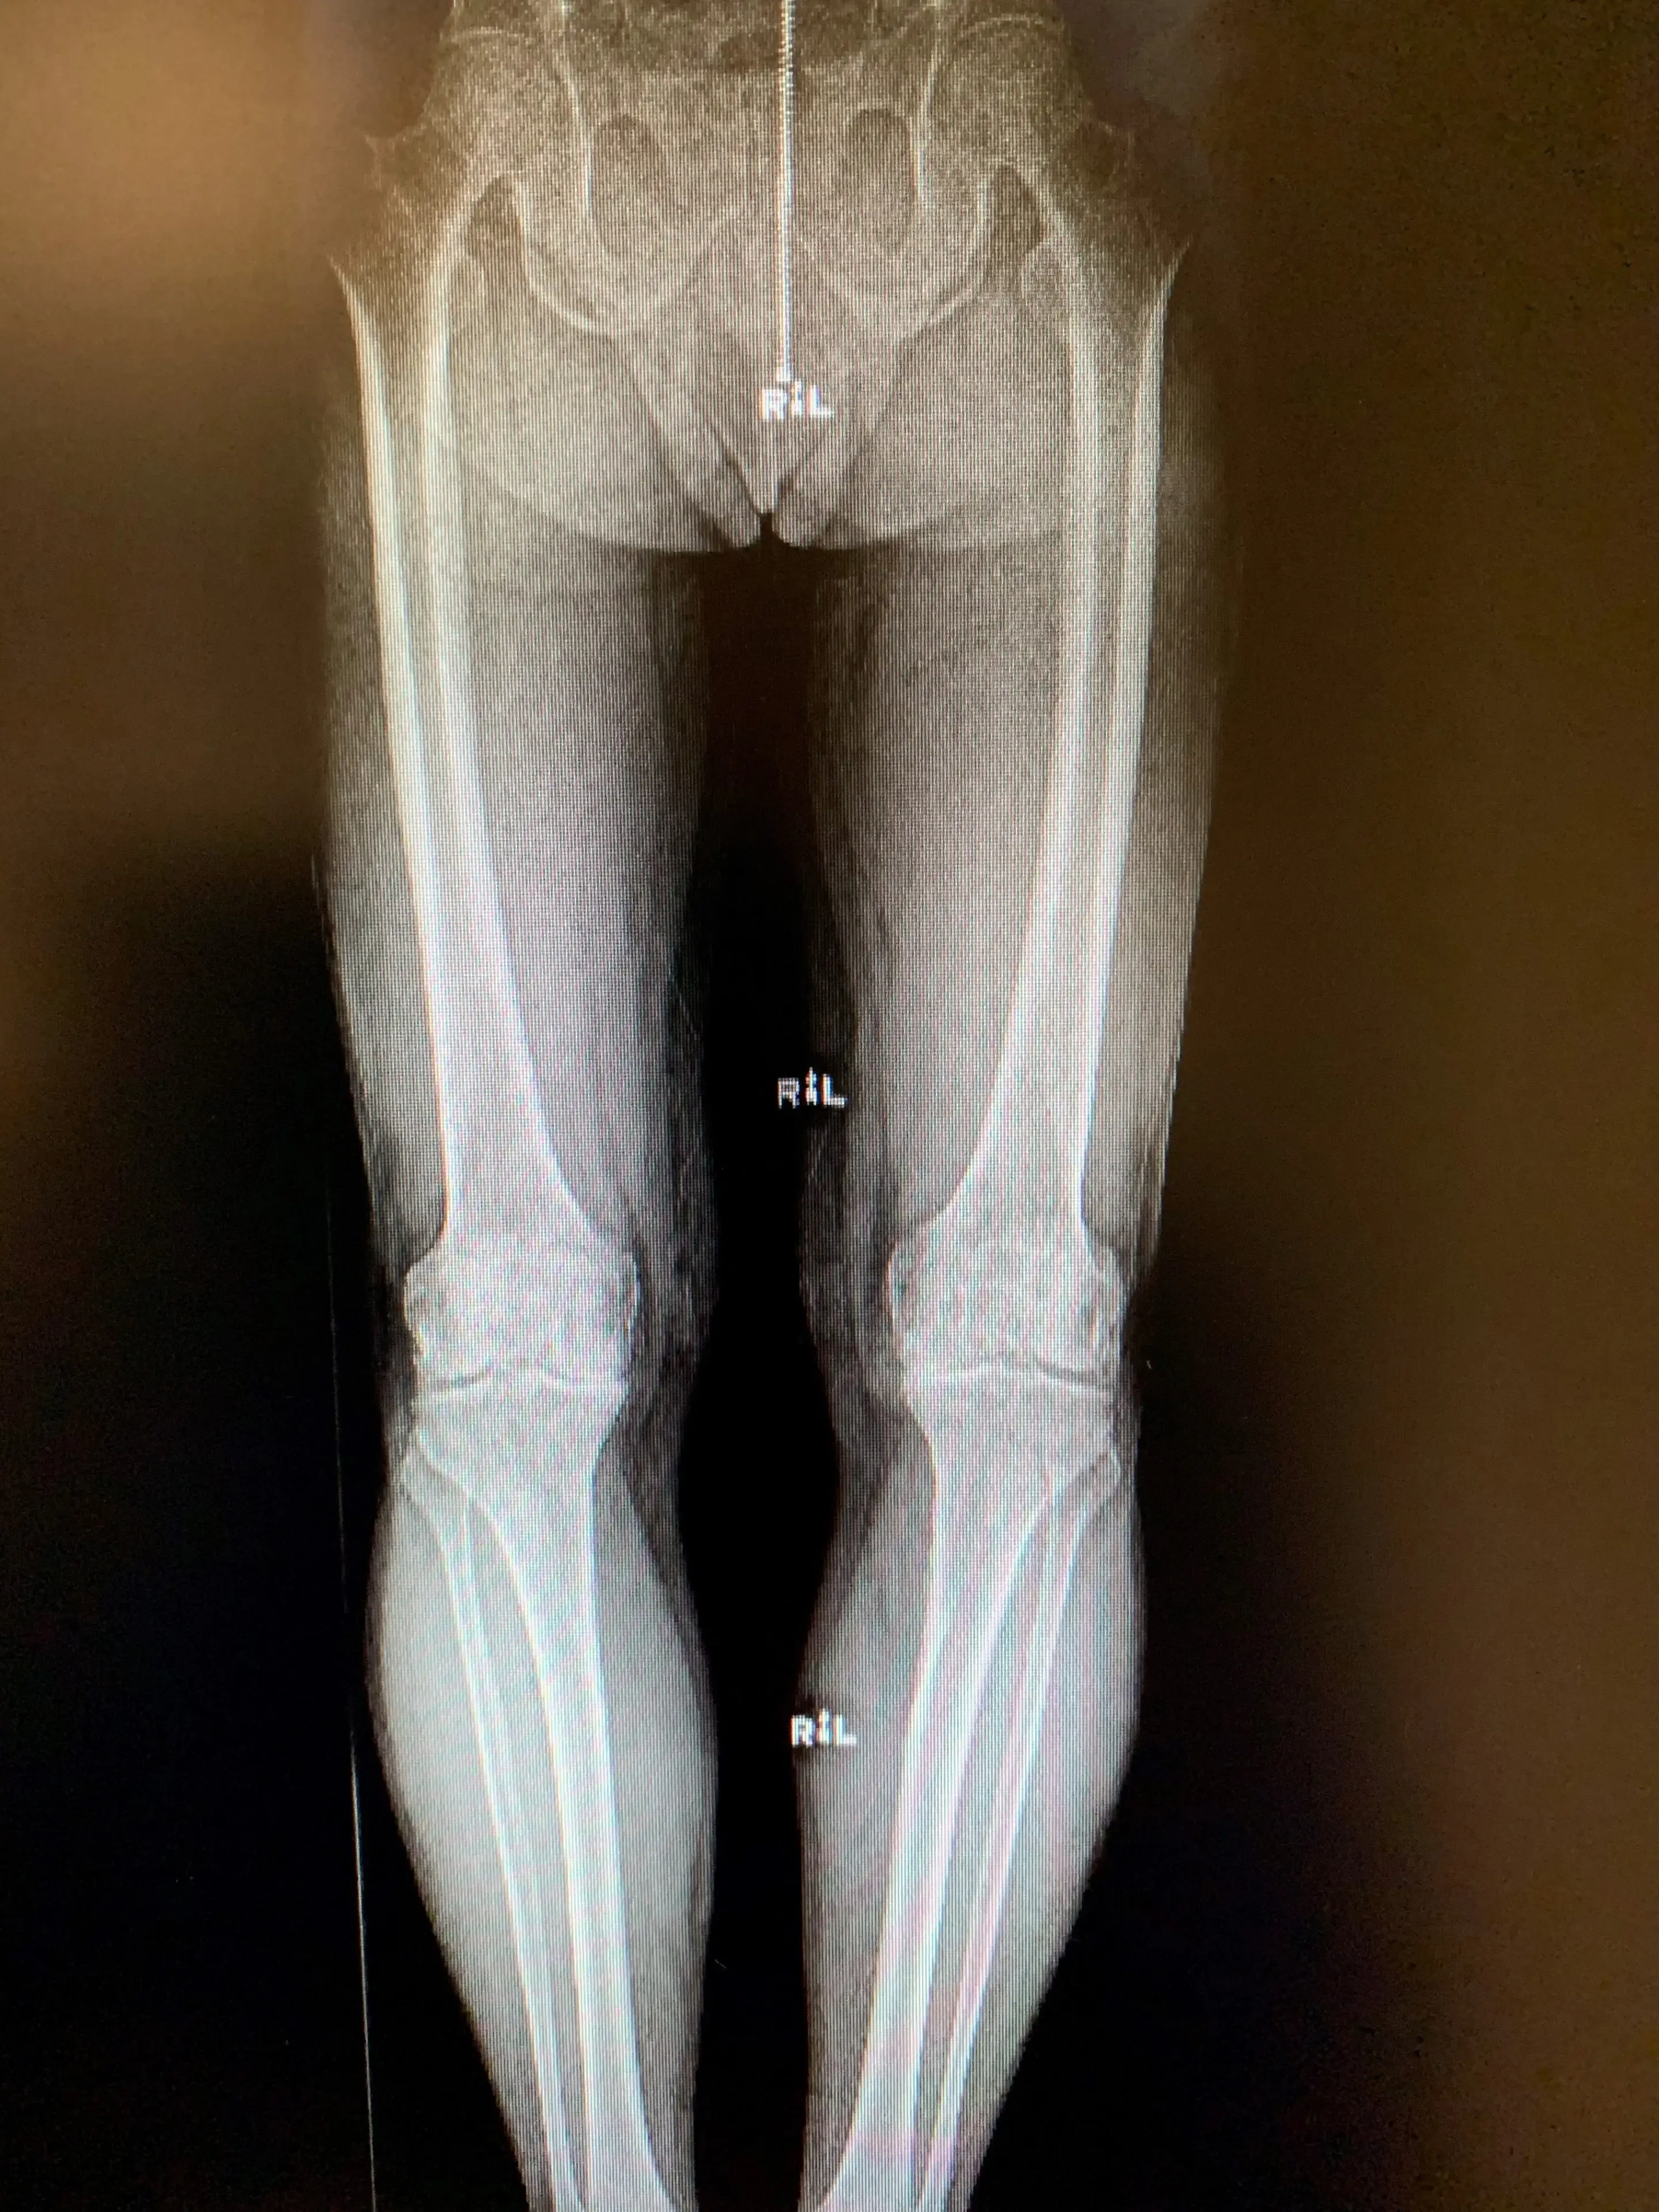

Sus radiografías de película sencillas revelaron cambios artríticos en ambas rodillas confinados a su compartimento medial. La extensión de su artritis era aproximadamente igual en ambas rodillas y no presentaba deformidades radiográficas importantes.

Su examen físico fue en gran parte discreto, salvo por cierta sensibilidad en la línea articular medial en ambos lados. Específicamente, no tenía contractura de flexión y su LCA estaba funcionalmente intacto. Tenía una pequeña alineación varus totalmente corregible en ambas rodillas.

Preoperatorio![]()

Reemplazo bilateral simultáneo de rodilla unicóndilo en un hombre de 67 años.